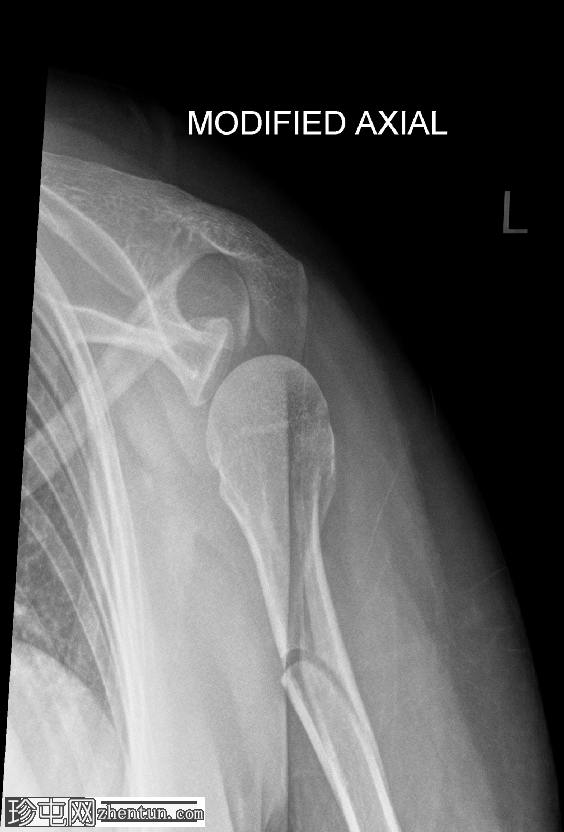

X线片

1.png

正位

肱骨近端粉碎性移位骨折,累及骨干近端半部、外科颈,并延伸至大结节。

肱骨头在肩关节内向下半脱位,肩峰肱骨间距增大。